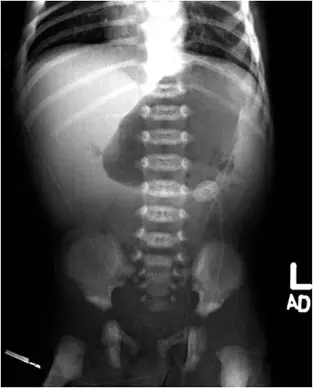

病患為10天大男嬰,腹部側位平片可見:

- 上腹部有明顯氣體積聚,呈現類似「雙氣泡(double bubble)」或近端小腸迴盪擴張。

- 遠端腸道氣體稀少,顯示近端阻塞。

- 無明顯游離氣體(排除腸穿孔)。

這些特徵符合高位小腸阻塞,而在新生兒中最顧慮的即是malrotation併發的midgut volvulus。